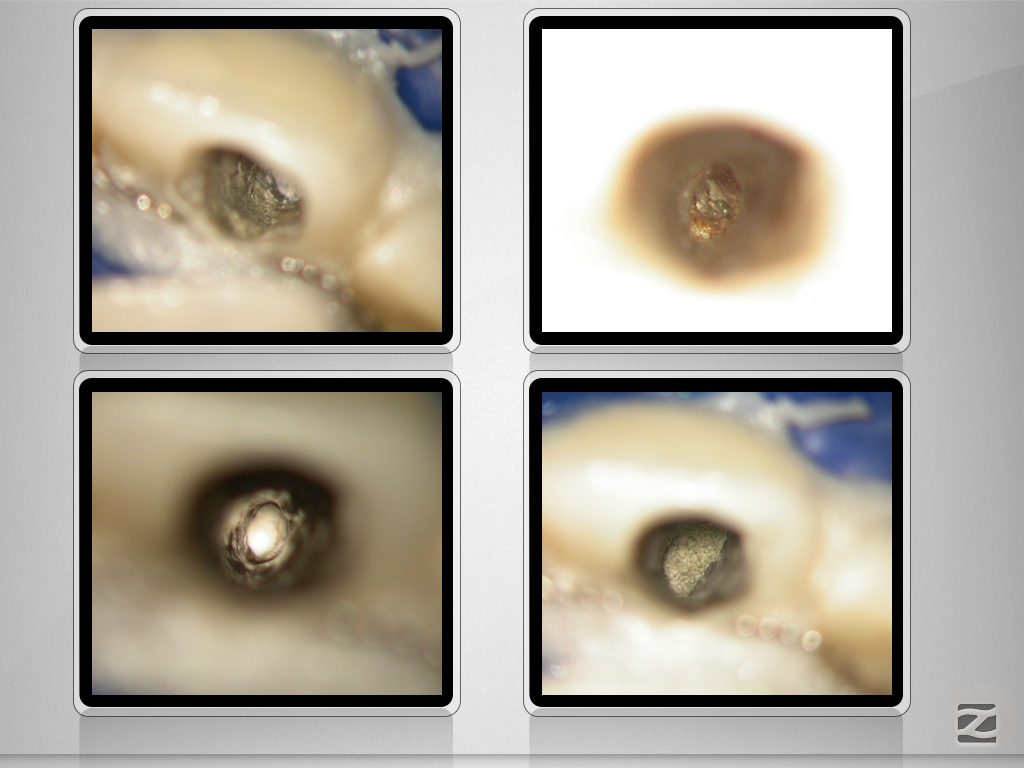

11D.007

An der Grenze …